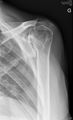

- Différentes lésion labrales post.jpg Alexandre.laedermann

19:53, 26 January 2020

1,918 × 454; 739 KB